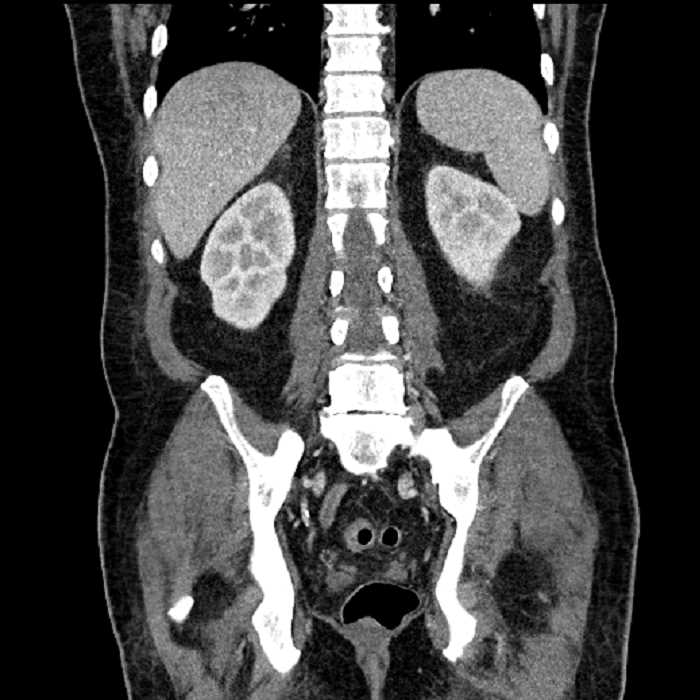

Age: 63

Sex: Male

Indication: Abdominal pain

• Large fluid density structure in hepatic segments 7 and 8 measuring 10 x 7 x 7 cm with internal septation and circumferential ill-defined low density compatible with edema

• Peripherally enhancing subcapsular collections along the anterior margin of the left hepatic lobe measuring 3 x 1 cm and 2 x 1 cm

• Clearly marginated fluid density structure in segment 7 and several other scattered tiny hypodensities, which likely represent cysts

• Hepatic abscess

Acute sigmoid diverticulitis complicated by a small contained perforation and a large abscess in the right hepatic lobe. Additional small subcapsular abscesses along the anterior margin of the left hepatic lobe.

Additionally, loss of the normal fat plane between the peridiverticular collection and adjacent thickened loops of small bowel raises the potential for an enterocolonic fistula.

• The classic CT imaging appearance is a double target sign with internal low density surrounded by an internal enhancing rim (capsule) and a low density external rim (edema)

Hepatic abscess showing the double target sign with low density internally surrounded by a thin inner enhancing rim (red arrow) and ill-defined outer low density rim (yellow arrow). Blue arrow indicates an internal septation. Red arrows: additional smaller subcapsular abscesses. Red arrow: focal contained perforation associated with diverticulitis.